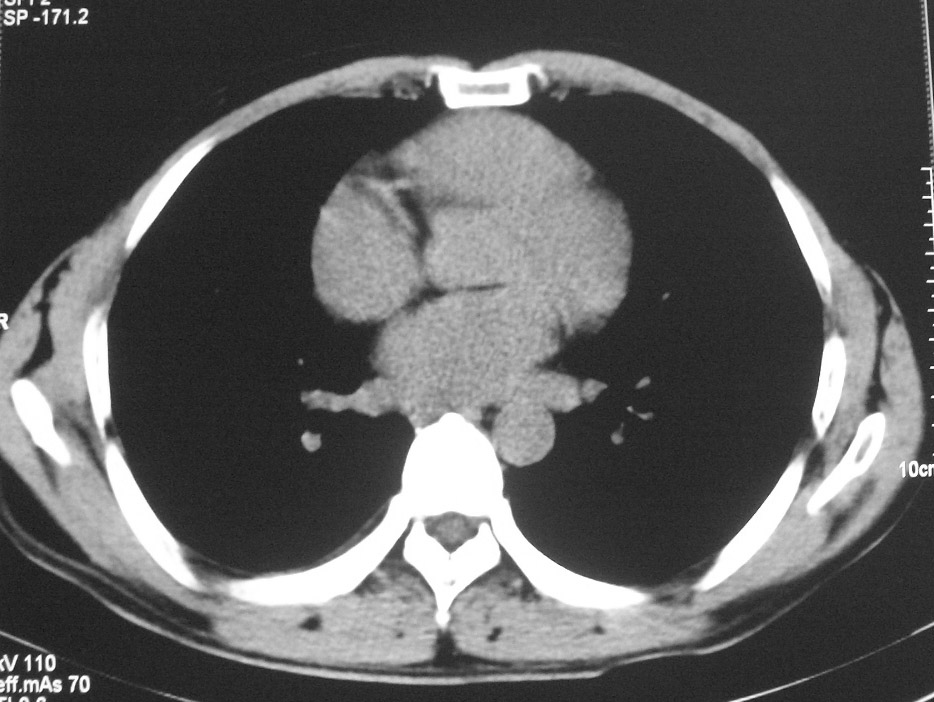

标题: CT5485:[原创]肺部占位请讨论

右上肺ca并肺不张,纵隔淋巴结转移

右肺上叶中央型肺癌并上叶肺不张、纵隔淋巴结肿大

右上叶支气管后壁明显增厚,支持右肺上叶中央型肺癌伴右上叶肺不张、纵隔淋巴结肿大。

考虑右上肺癌并肺不张,纵隔淋巴结转移

右上叶支气管后壁明显增厚,支持右肺上叶中央型肺癌伴右上叶肺不张、纵隔淋巴结肿大。建议支气管镜检查。

右上肺中央性肺癌伴右侧胸腔少量积液!右上肺胸膜下还有一小病灶,不完全排除结核,但个人支持恶性肿瘤!建议早穿刺活检。

右上叶支气管开口变窄,纵隔见肿大的淋巴结。支持右上叶中心型肺癌并右上叶不张纵隔淋巴结肿大。

右肺上叶中央型肺癌并上叶肺不张、纵隔淋巴结肿大.右侧少量胸腔积液。

右上肺中心型肺癌并肺不张,纵膈淋巴结肿大。右侧少量胸腔积液。

右肺上叶支气管后壁增厚,呈鼠尾状狭窄,纵隔内未见明显增大的淋巴结影,考虑为中央型肺癌伴右上肺不张